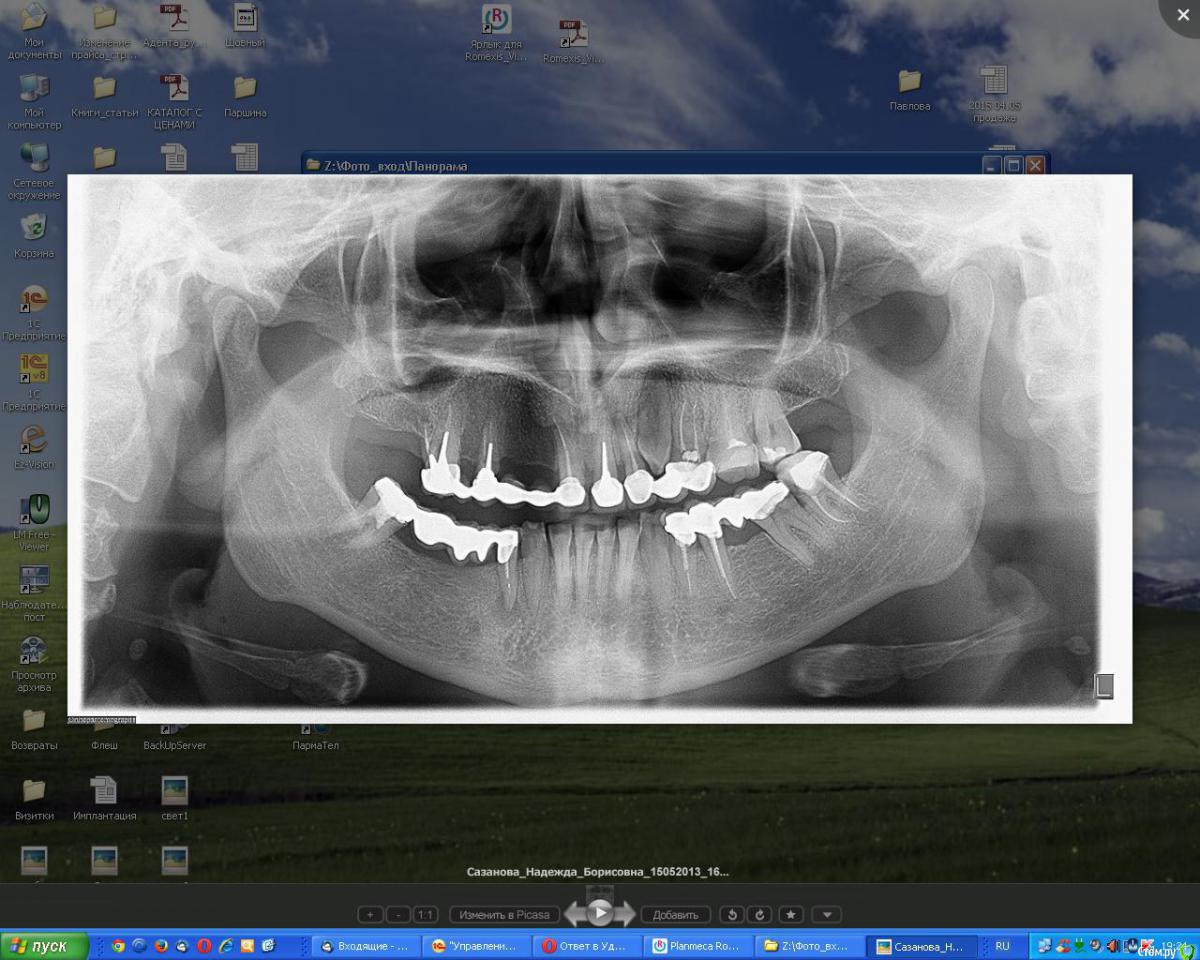

Михаил Петрушко Опубликовано 29 июня, 2015 Автор Поделиться Опубликовано 29 июня, 2015 Если третий моляр нижней челюсти ретинирован и дистопирован, как он может повлиять на рецидив лечения? И для чего там нужно место? Я объясню мой вопрос. Приходит, например, молодая девушка со скученностью нижних зубов, девушке к примеру 18 лет или 28 (много аналогичных случаев было). Ортодонт велит удалить все зачатки, чтобы, как я понимаю, дистально сдвинуть зубной ряд и освободить место для исправления положения зубов во фронтальной группе. При микрогнатии, даже совсем небольшой, челюсть вряд ли вырастет в таком возрасте. Итог лечения, зубы стоят ровно, но во фронтальном отделе дикая рецессия десны, которую мне же потом закрывать пластикой. Так зачем удаляли восьмерки??? Ссылка на комментарий

Ker Опубликовано 30 июня, 2015 Поделиться Опубликовано 30 июня, 2015 Если третий моляр нижней челюсти ретинирован и дистопирован, как он может повлиять на рецидив лечения? И для чего там нужно место? Я объясню мой вопрос. Приходит, например, молодая девушка со скученностью нижних зубов, девушке к примеру 18 лет или 28 (много аналогичных случаев было). Полагаю надо индивидуально смотреть. Он ведь и прорезаться может, тем более 18 лет.А по поводу рецессии это точно не вина восьмерок. Ссылка на комментарий

Bier Опубликовано 1 июля, 2015 Поделиться Опубликовано 1 июля, 2015 Мое мнение, что зачатки 8рок надо удалять почти всем в подростковом возрасте, пока они не отрастили корни, не зацепились за нерв, пока не испортили семерки, пока не сдвинули зубы. В общем 15-17 лет самый возраст для того чтобы безопасно и быстро избавить человека от проблем в дальнейшем. 9 Ссылка на комментарий

zzkz Опубликовано 17 июля, 2015 Поделиться Опубликовано 17 июля, 2015 тоже удаляю такие 8-ки довольно часто.единственный не понятный момент, когда в 15-17 лет зачатки еще глубоко, особенно на в/ч, стоит ли ждать и отслеживать их рост, чтобы удаление было менее травматичным? Ссылка на комментарий

Bier Опубликовано 18 июля, 2015 Поделиться Опубликовано 18 июля, 2015 тоже удаляю такие 8-ки довольно часто.единственный не понятный момент, когда в 15-17 лет зачатки еще глубоко, особенно на в/ч, стоит ли ждать и отслеживать их рост, чтобы удаление было менее травматичным?С верхними иногда прошу подождать до 18-19 1 Ссылка на комментарий